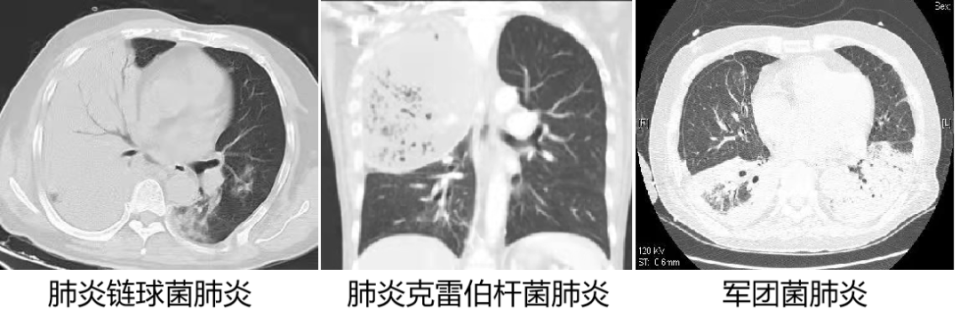

1. 肺泡性肺炎:由多个肺小叶组成亚段或段的片状影,严格按解剖区域出现(肺链最典型,军团、肺克稍差)。

1. 大叶性肺炎(肺泡性肺炎):渗出性病变占满一个或几个肺叶,这时称大叶性肺炎。

1. 肺泡性肺炎(大叶性肺炎):肺炎链球菌肺炎、肺炎克雷伯杆菌肺炎、军团菌肺炎及肺隐球菌病。